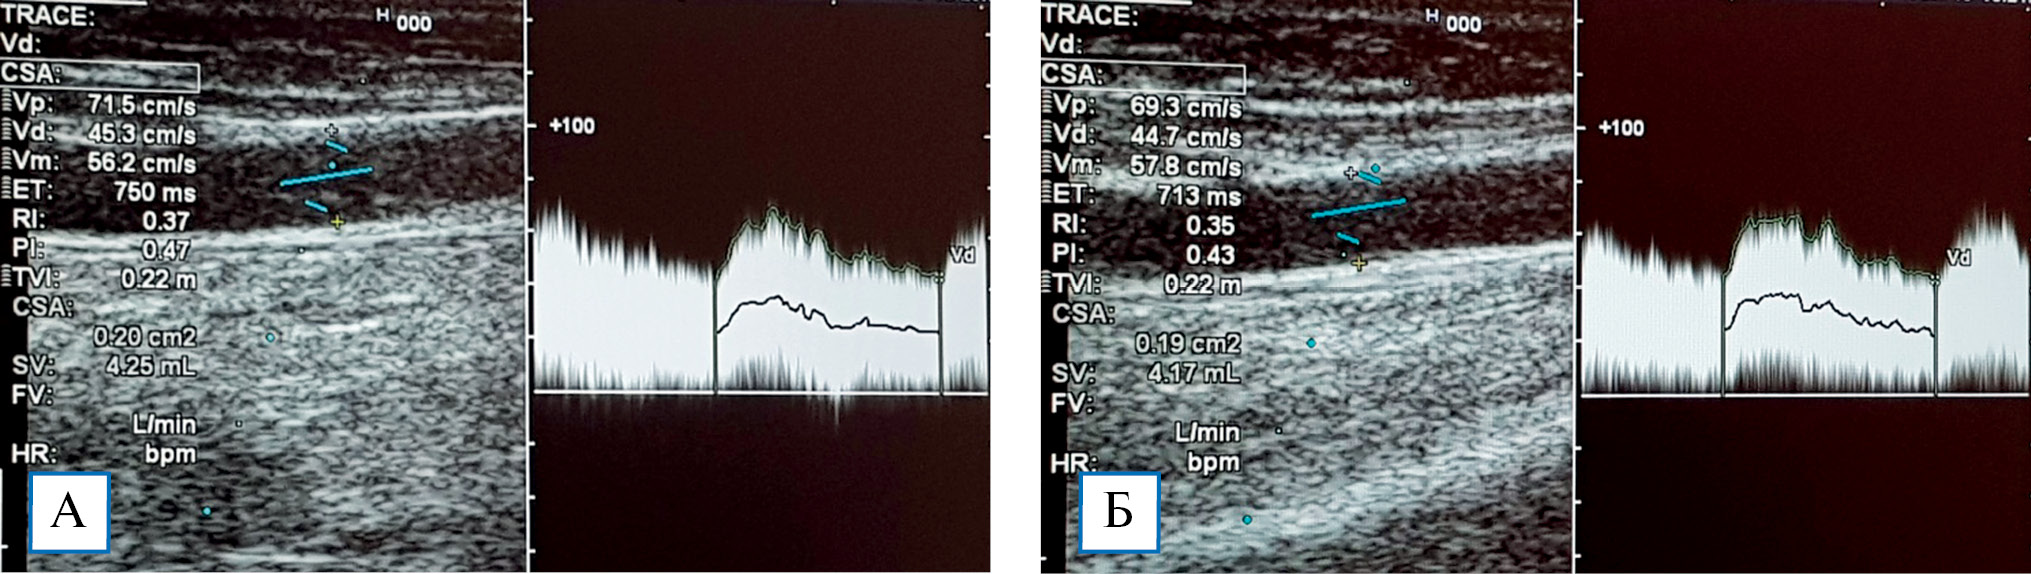

При пробе с физической нагрузкой у пациентов без стил-синдрома наблюдалось увеличение показателя ОСК на 29,3 ± 4,6% (рис. 3). Снижение тонуса резистивных сосудов при физической нагрузке способствует увеличению притока крови в микроциркуляторное русло кисти, что является важным механизмом ауторегуляции кровотока и адаптации к гипоперфузии. При стил-синдроме в ответ на физическую нагрузку реакция отсутствовала, что указывает на срыв компенсаторных механизмов регуляции кровотока в кисти (рис. 4).

Рис. 3. Эхограммы локтевой артерии: объемная скорость кровотока исходно (А) составила 610 мл/ мин, после пробы с физической нагрузкой (Б) — до 868 мл/мин (увеличение на 30,0%)

Рис. 4. Эхограммы локтевой артерии: объемная скорость кровотока исходно составила 425 мл/мин (А), ее снижение после пробы с физической нагрузкой до 417 мл/мин свидетельствует о срыве компенсаторных механизмов ауторегуляции кровотока в кисти (Б)